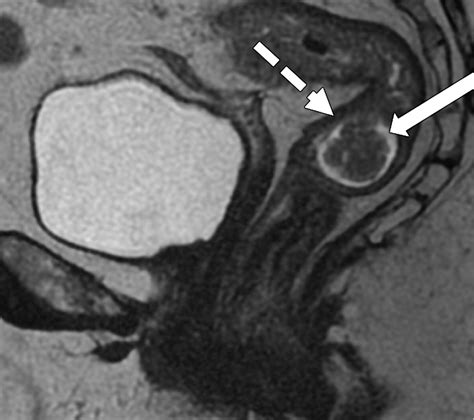

Imaging (MRI/CT) Assesses the extent and spread of the disease.